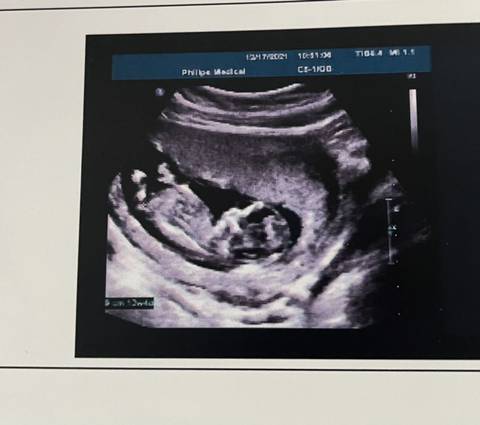

12周多的B超,能看出男女吗?

journal_insert_pic_1684272727

你好。我们是判断不了男宝宝跟女宝宝的,孕期定期检查,我觉得宝宝健康就好的。祝心想事成 。

你好,从这上面看不出宝宝的性别,不管宝宝是男孩还是女孩,只要宝宝健健康康就好,祝你心想事成。

看不出来,这个普通人是很难直接判断男孩还是女孩的哦,其实只要孩子健健康康就好,生下来才最准

亲爱的,通过这些判断不出来是什么样性别的哈,反正宝宝发育好就是最好的哈,祝你好孕。